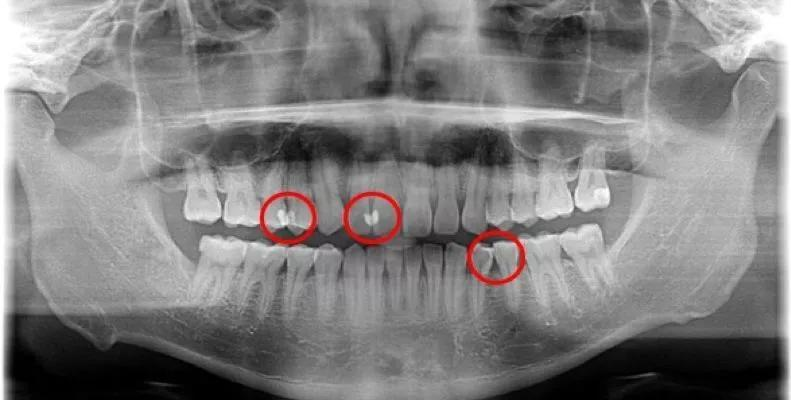

所以需要牙科ct(牙片)才能够观察到牙齿各项不易观察到的异常状态,包括邻面龋。

▶ 红色区域均为邻面龋

那么,②「口腔检查」就需要定期进行了,不仅利于自己了解牙齿的生长状态,还能够及时发现病征。

引自德国先进的数字化Sirona CBCT设备,只需要2分钟就能够扫描到全面的口内数据,以三维立体的高清图像形式展现出来。

肉眼观察不到的异常(早期邻面龋),医生和患者都能够一目了然。